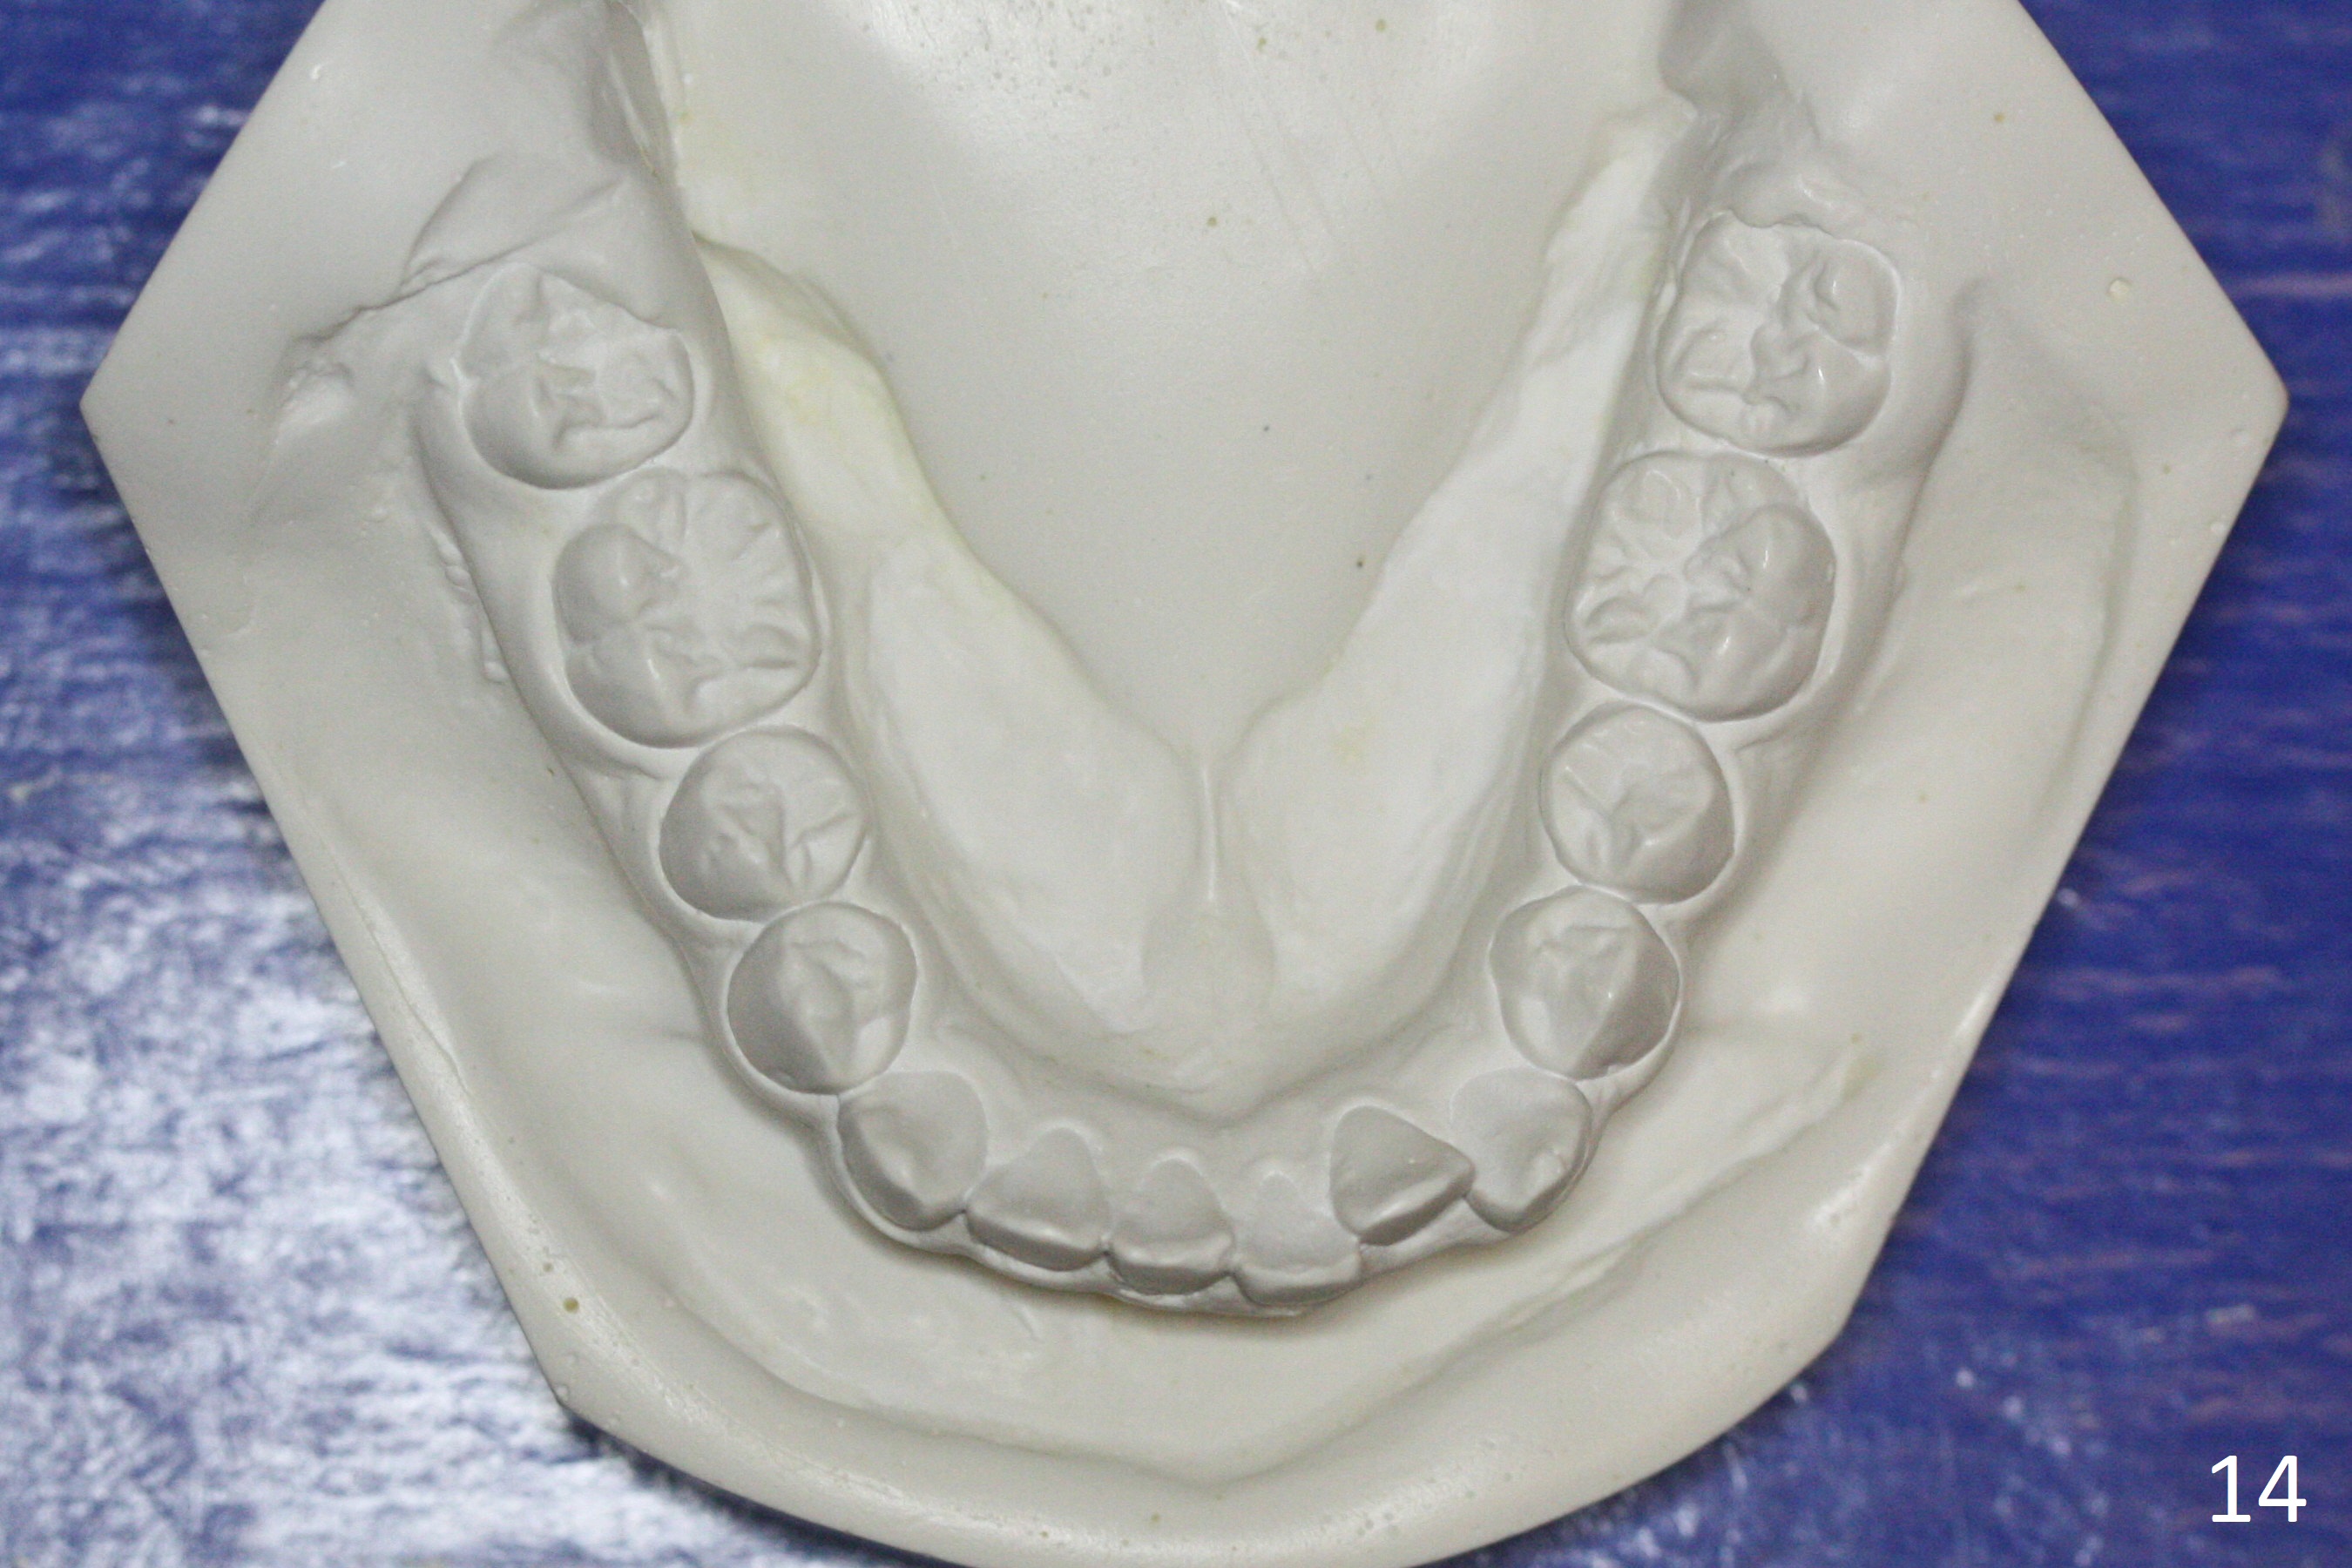

A 12-year-old woman has normal facial profile (Fig.1-6,12) and crowded dentition (7-11). Because of erupting 2nd molars (Fig.10,15), it is difficult to place rubber separators between U6/7. Copper ones are used instead (Fig.15 ^). Crowding and narrow arches (Fig.13,14) may be associated with the enlarged right Inferior Nasal Concha (Fig.15 *).